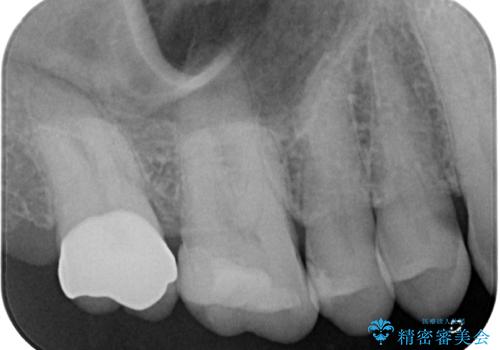

部分的な詰め物では再び割れてしまう可能性が高いため、虫歯を除去し、オールセラミッククラウンにて補綴することとしました。

歯が欠けてしまってから数日で来院していただいたので、虫歯が大きく進行することなく、歯の神経の治療などせず、必要最小限の治療で済みました。